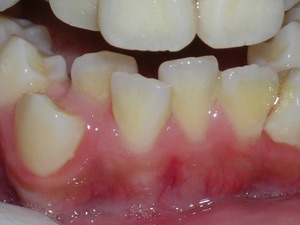

Here is what he looked like on the day that the braces were removed.

In the final photo, you can see the bonded retainer we used. A top nighttime removable retainer was made.